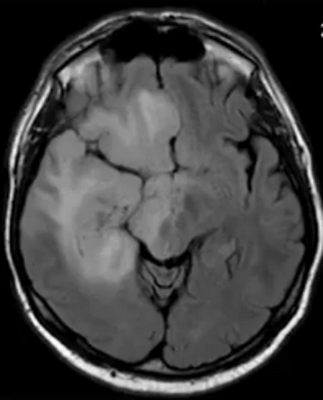

Глиобластома на МРТ головного мозга без контраста

- глиобластомы — злокачественные опухоли, которые отличаются высокой скоростью роста и склонностью к инвазии. Выглядят на снимках, как образования неправильной формы, с нечеткими фестончатыми контурами и выраженным перифокальным отеком. Дают выраженный масс-эффект, смещают головной мозг в полости черепа, повреждая его на отдалении от своего местоположения;